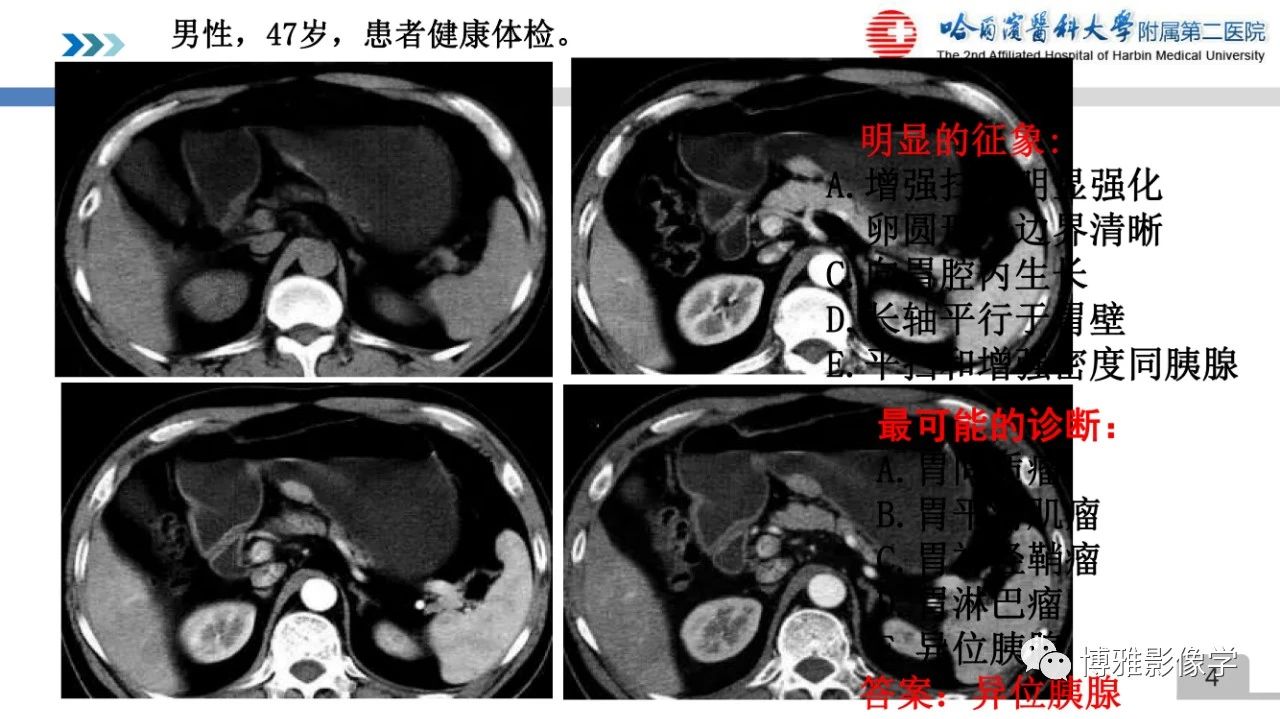

异位胰腺